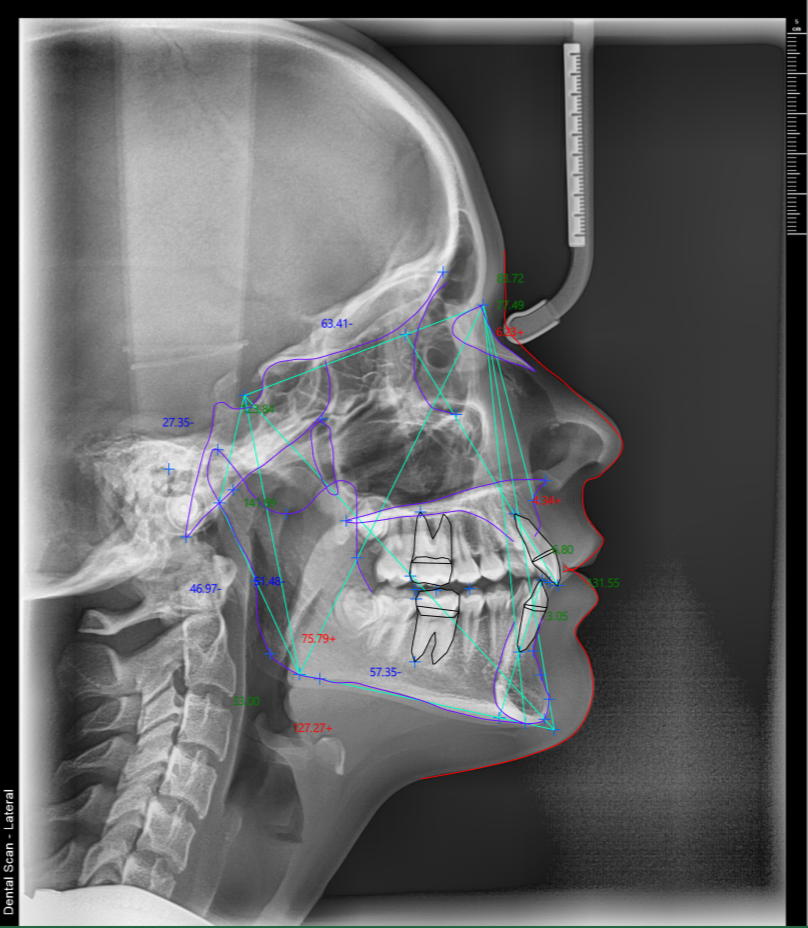

Kefalogram, poznat i kao telerendgen ili lateralni cefalogram (eng. Lateral Cephalometric Radiograph – LCR), standardizovani je rendgenski snimak glave koja se koristi pre svega u ortodontskoj dijagnostici i planiranju terapije. Reč je o preciznom snimku koji pruža uvid u međusobni odnos vilica, zuba i kostiju lica — informacije koje nijedna druga vrsta snimanja ne može da pruži na ovaj način.

Zbog standardizovane tehnike, kefalogram je jedini rendgenski snimak na kome je moguće raditi pouzdanu kefalometrijsku analizu — niz merenja uglova i dužina na osnovu kojih se donose dijagnostičke i terapijske odluke.

Šta se vidi na kefalogramu?

Na lateralnom cefalogramu jasno se uočavaju sve ključne strukture lica i vilica, a najvažniji anatomski elementi su:

- Sela turcika (S) — centralna referentna tačka lobanje

- Nasion (N) — tačka nazofrontalne suture

- Tačka A — najdublja tačka prednje konture gornje vilice (maksile)

- Tačka B — najdublja tačka prednje konture simfize donje vilice (mandibule)

- Gonion (Go) — najniži ugao mandibule

- Menton (Me) — najniža tačka simfize mandibule

- ANS i PNS — prednja i zadnja nosna bodlja

Ove anatomske tačke su osnova za crtanje kefalometrijskih ravni i uglova koji definišu dijagnozu.

Kefalometrijska analiza — merenja i referentne vrednosti

Nakon što se snimak napravi, ortodont vrši kefalometrijsku analizu — ručno ili digitalnim softverom — mereci ključne uglove i odnose. Najvažniji parametri su:

| Merenje | Prosečna vrednost (Eastman standard) |

|---|---|

| SNA ugao | 81° ± 3° |

| SNB ugao | 78° ± 3° |

| ANB ugao | 3° ± 2° |

| Ugao gornjeg sekutića prema maksilarnoj ravni | 109° ± 6° |

| Ugao donjeg sekutića prema mandibularnoj ravni | 93° ± 6° |

| Interincizalni ugao | 135° ± 10° |

| MMPA (maksilomandibularni ugao) | 27° ± 4° |

| Proporcija lica | 55% ± 2% |

SNA i SNB uglovi pokazuju anteroposteriorni položaj gornje, odnosno donje vilice u odnosu na bazu lobanje. ANB ugao — razlika između SNA i SNB — određuje skeletnu klasu pacijenta: vrednost 2–4° odgovara Klasi I, ispod 2° je Klasa III, a iznad 4° Klasa II. Ovo je jedna od ključnih informacija za planiranje ortodontskog lečenja.

MMPA ugao (između maksilarne i mandibularne ravni) govori o vertikalnom obrascu rasta vilice — povećan ugao ukazuje na zadnji obrazac rasta i smanjen prepklop sekutića.

Savremeni digitalni kefalogrami omogućavaju ortodontima da kefalometrijsku analizu rade direktno u softveru, automatski ili poluautomatski — što smanjuje grešku i ubrzava planiranje terapije. Ako ste ortodont koji šalje pacijente na kefalogram, naši snimci su u DICOM formatu i kompatibilni sa vodećim ortodontskim softverima za analizu. Kontaktirajte nas za detalje o saradnji.

Po nalogu Ortodonta možemo uraditi preciznu automatsku analizu Telerendgen snimka uz pomoć veštačke intelingencije. Dostupne su Vam sledeće analize: